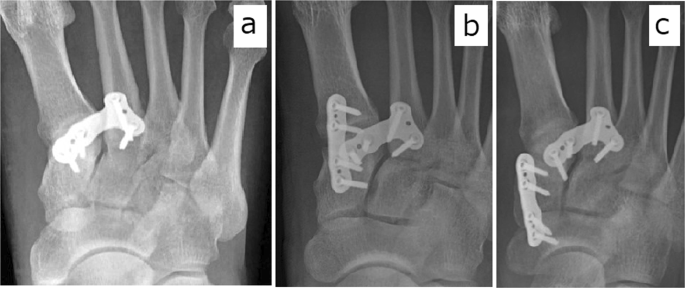

Our surgical decision-making process lies beyond the scope of our study. We note, however, that we have learned, over the study period, to observe some basic guidelines for Lisfranc injury fixation, as follows: In cases of simple longitudinal type injury, transverse type injury, or combination longitudinal and transverse type injury, we fix the joint between C1 and M2 (Figs 1a,b,d and 3a). In cases of a transverse type injury, the second TMT joint usually stabilizes after this C1–M2 fixation. In cases of a transverse type and first TMT joint injury (Fig. 1c), longitudinal type and first TMT joint injury (Fig. 1e), or combination longitudinal type, transverse type, and first TMT joint injury (Fig. 1f), we fix the first TMT joint as well as the joint between C1 and M2 (Fig. 3b). In cases of a longitudinal injury extending into the naviculo-first cuneiform joint (Fig. 1g), we fix the joint between C1 and M2 as well as the naviculo-first cuneiform joint (Fig. 3c). Additional study is needed to validate these guidelines.

Postoperative radiographs of longitudinal type injury (a), transverse type injury combined with first tarsometatarsal joint injury (b), and Longitudinal injury extending into the naviculo-first cuneiform joint (c).